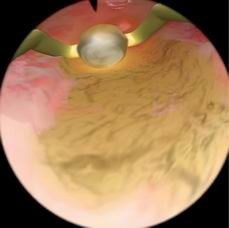

肌瘤切除模块

病例由易到难,简单的病例可发生在子宫底部,复杂的病例可发生在子宫前壁或者靠近输卵管口的地方